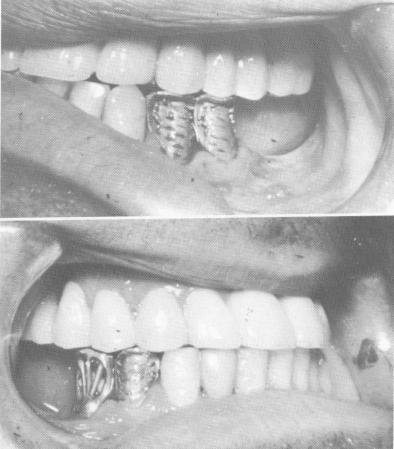

Fig. 15-27. Lower veneer crown castings are to meet the remaining interocclusal space.

A wax interocclusal record of centric relation was made, and a full arch maxillary plaster index was taken for the fabrication of a full arch splint constructed in three quadrants (Fig. 15-26). The two posterior acrylic-and-gold veneer bridges were interlocked with gold dovetails into deep rest seats that existed in the cuspid restorations of the anterior porcelain-baked-to-metal restoration. Lower castings were processed to close the "gap" that existed by bisecting the imaginary plane (Fig. 15-27) .

1 Lower veneer crown castings are to meet remaining interocclusal space